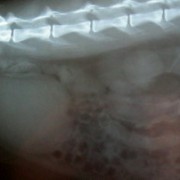

Onder narcose is goed te zien hoe vast de haak in het slijmvlies zit